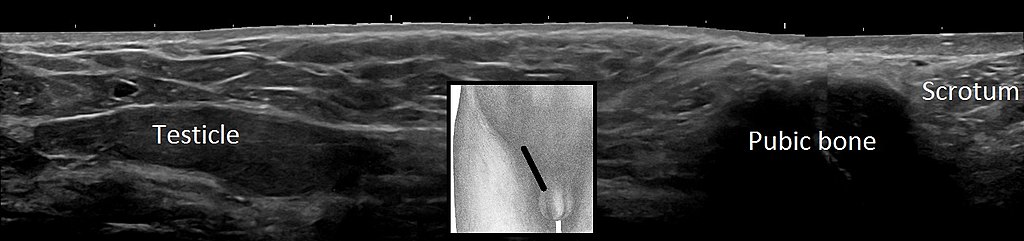

Varicocele is the dilation of the spermatic vein because of impaired drainage.

Varicocele presents as a “bag of worms” like scrotal enlargement.

Varicoceles are typically left sided.

The left testicular vein drains into the left renal vein.